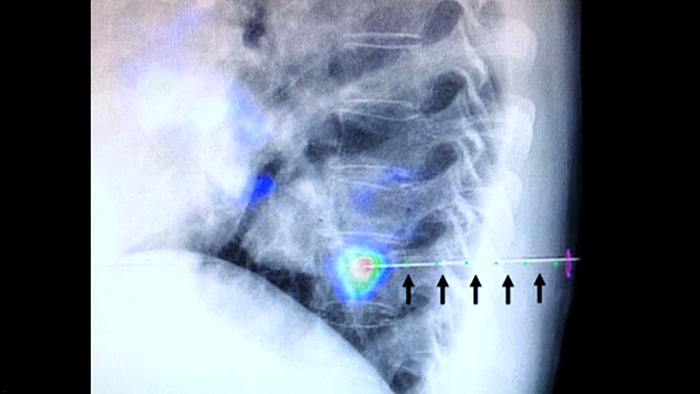

XperGuide fournit un guidage par imagerie en temps réel très précis de chaque aiguille vers une position cible en superposant les trajectoires préplanifiées avec l’imagerie fluoroscopique.3

Une navigation précise à faible dose vers la lésion concernée sans repositionnement de l’aiguille augmente les chances de réussite et réduit le risque de complications de vos biopsies ou de vos ablations. La confirmation du point final du traitement d’ablation s’effectue avec l’imagerie 3D lorsque le patient est encore sur la table.